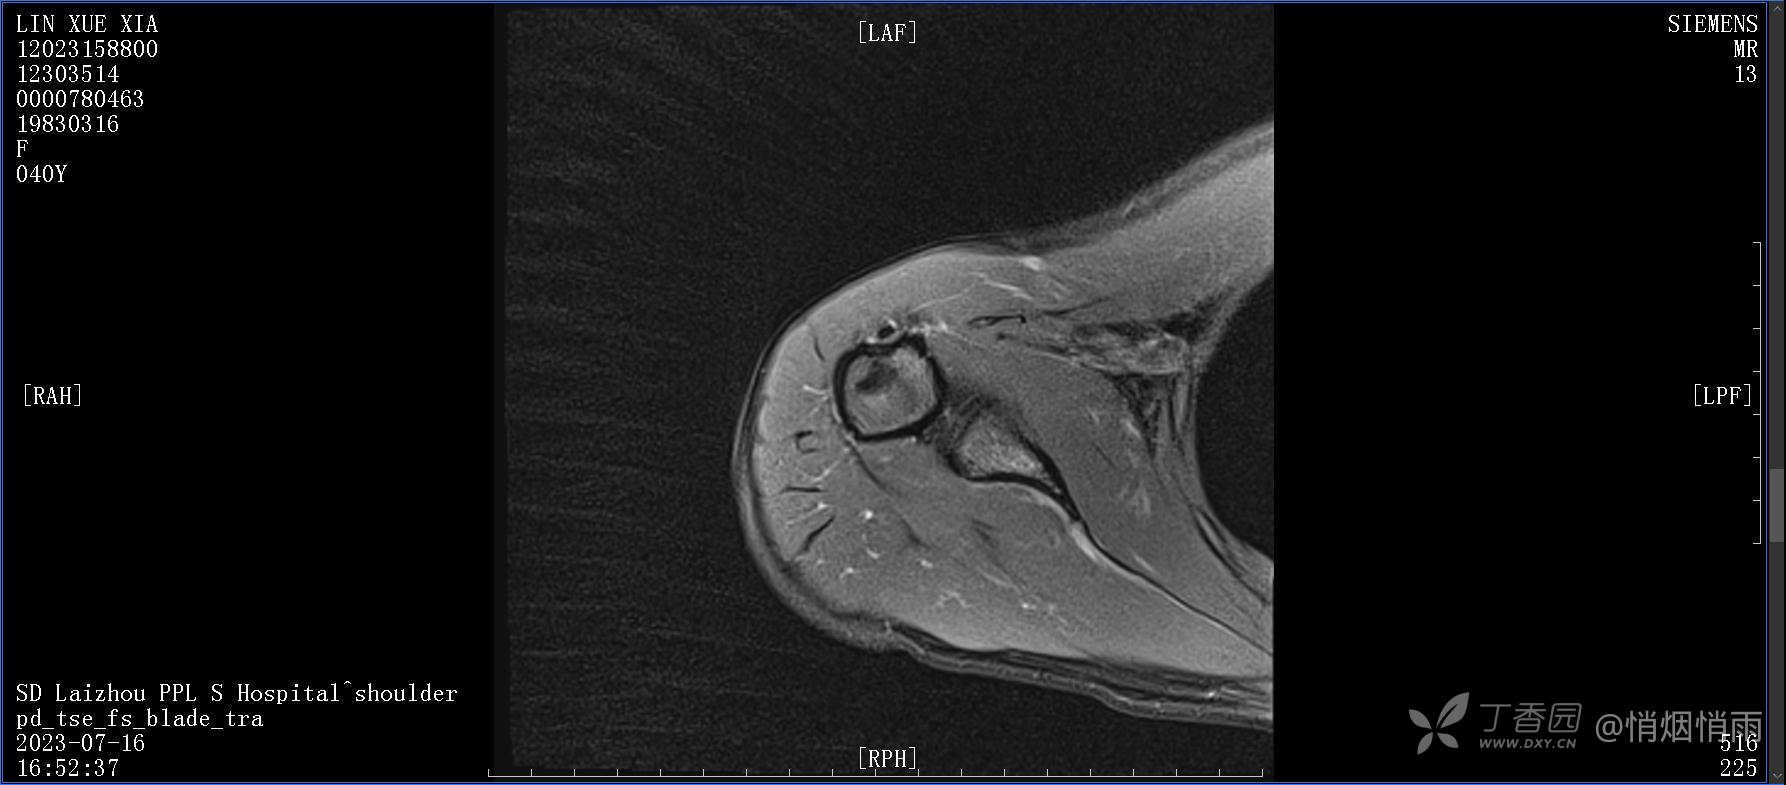

查体:右肩关节局部轻度肿胀,肩胛区压痛明显,痛处不固定,肩关节痛性活动受限,jobe test(+),lift -off test(+),中指、环指感觉较余指减退,余肢端感觉及血运情况可。

目前的诊断,暂时依据辅助检查诊为肩袖损伤,但是患者疼痛的性质和特点,却不是单纯的肩袖损伤所致。考虑过胸廓出口综合征,但是该疾病会出现肩胛区的疼痛吗?(由于考虑到费用的问题,没再进行下一步的检查)带状疱疹会有如此的症状吗?